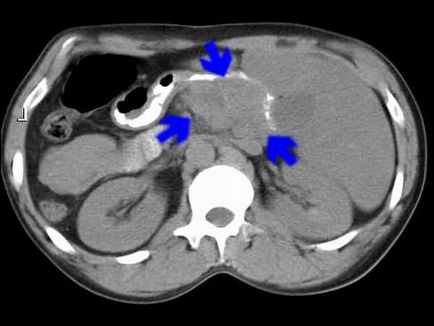

- УЗД pancreas (наявність гіпертрофії, зміна структури проток і тканини залози, відсутність / наявність кальцинатів).

- КТ або МРТ (для виключення злоякісних новоутворень).